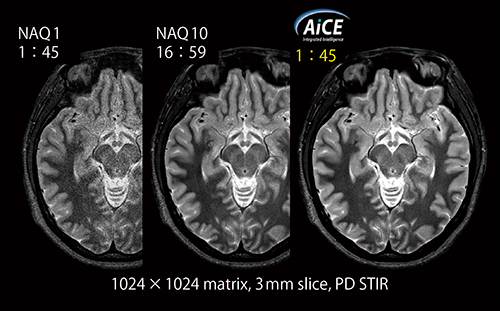

AiCEのデノイズ効果として,頭部高分解能撮像に適用した例を図5に示す。MRIでは撮像時間と分解能,SNRはトレードオフの関係にあり,分解能向上のために収集マトリックスを増加させるほど撮像時間は延長し,SNRは低下する。通常,1024×1024マトリックスの高分解能画像では,加算回数(以下,NAQ)10で17分程度の撮像時間をかけなければ観察可能な画像にならないが,AiCEを適用したNAQ1の画像は,NAQ10相当のSNRが確保できている。

AiCEはさまざまな撮像に対して適用可能な技術であり,通常検査や高分解能検査を短時間で実施できる。

図5 AiCEのデノイズ効果